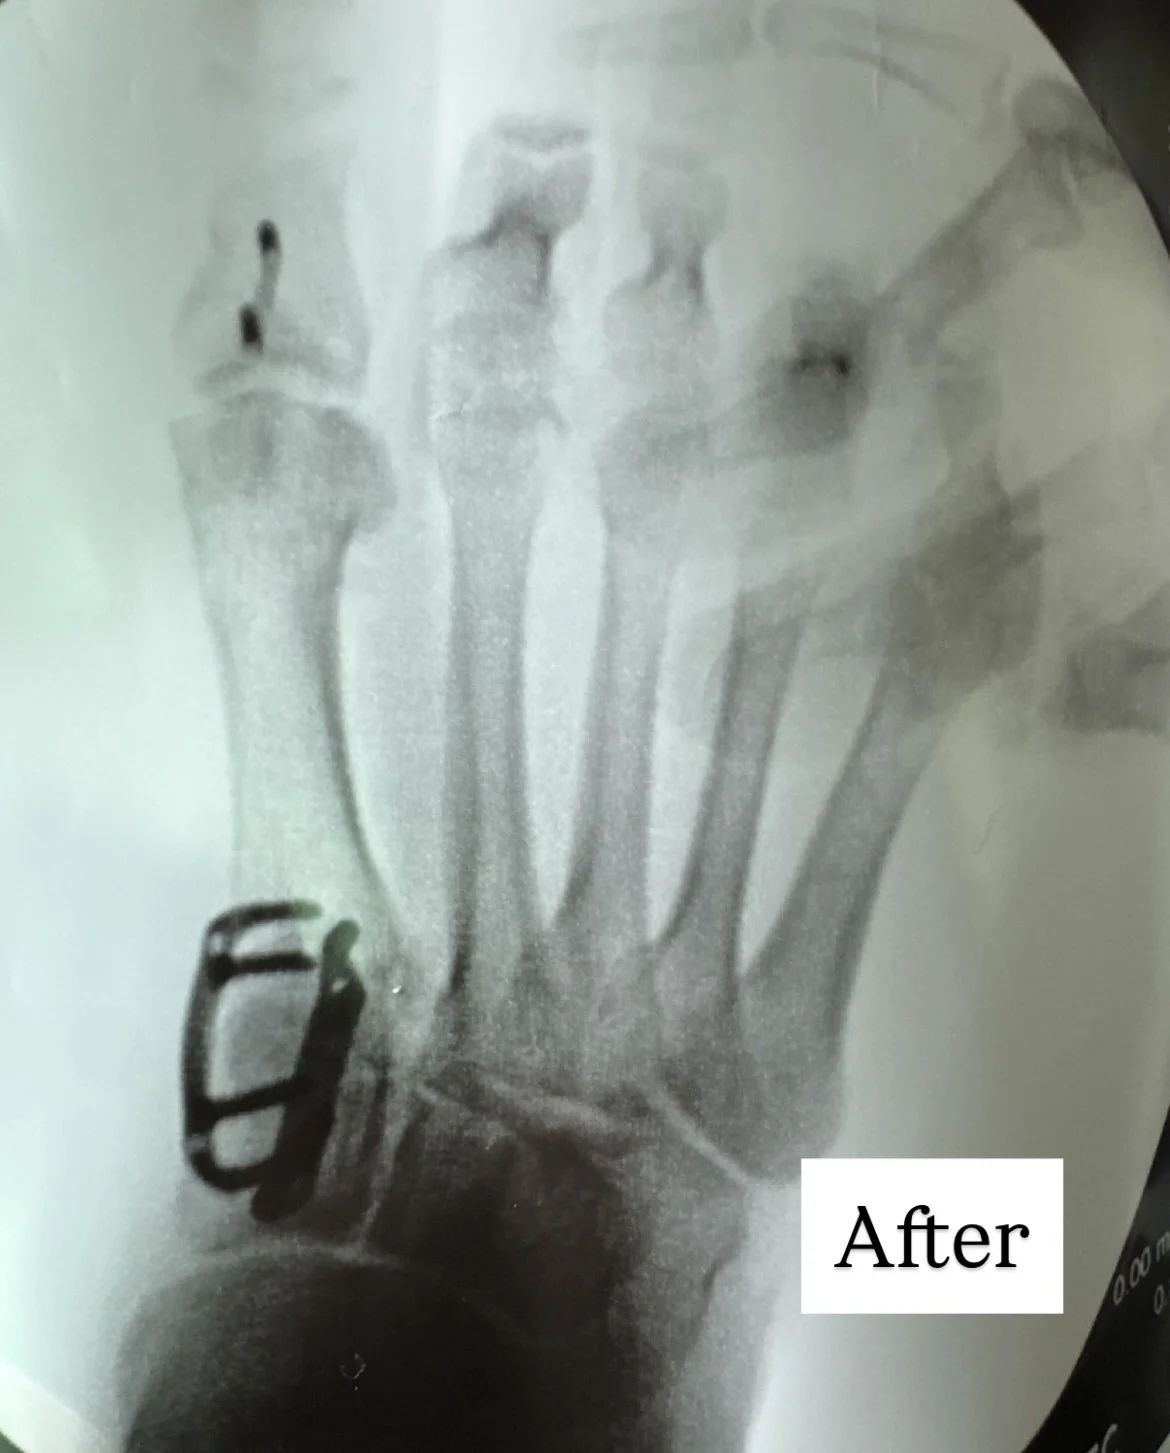

Dr. noah’s lapiplasty correction

97-99% of patients maintain their 3D correction (as demonstrated in 13 &17 month studies)